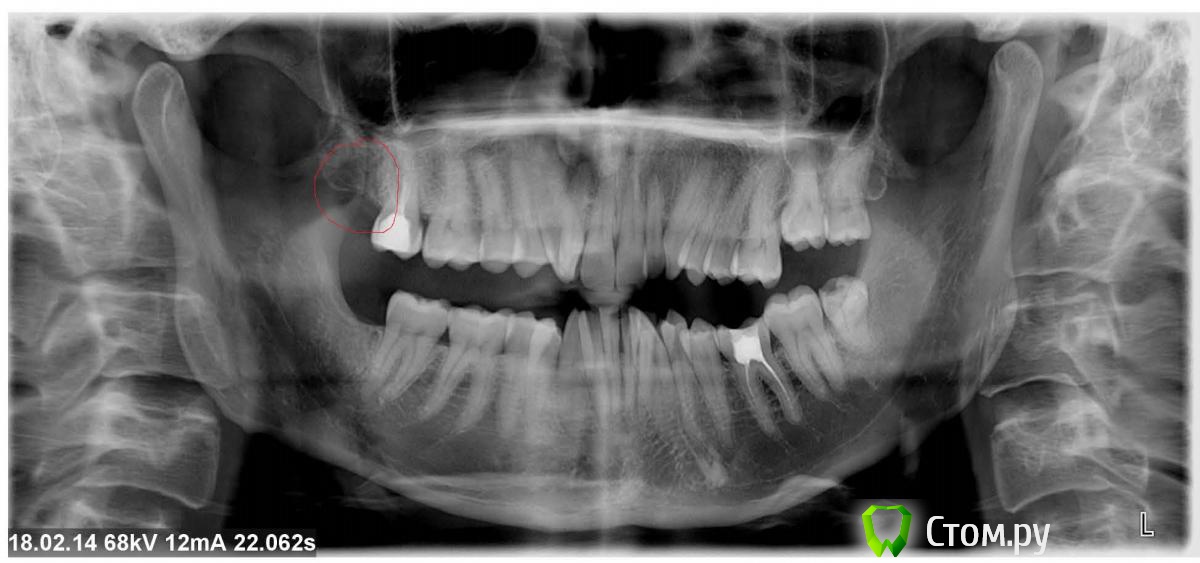

Анатолий М Опубликовано 18 февраля, 2014 Поделиться Опубликовано 18 февраля, 2014 Добрый день уважаемые форумчане. Не смог точно определить в какой раздел форума мне следует обратится.Коротко ситуация слудующая.Пол года хождения по врачам с болью в правой верхней части челлюсти.Боли не сильные. Скорее ноющие. Переодически усиливаются либо затихают. Иногда изчезают совсем. В течении дня такие перерывы часты.Бывают перерывы которые длятся от нескольких дней до нескольких недель. Когда ни каких болей нет совсем. Потом все начинается с начала.При постукивании шпателем по зубам все зубы никак не риагируют. Десна не воспалены. Видимых поталогий в полости рта не отмечается.По ночам болей нет совсем. Начинаются утром и то затихая то усиливаясь продолжаются в течении дня.Сначала врачи думали что проблема в верхней восьмерке. Удалили. Проблема не изчезла.Потом предположили что проблема в кариесе соседней семерки. Депульпировали семерку. Проблема не изчезла.Теперь часть врачей скланяется к версии невралгии троичного нерва. Но так как симптоматика не характерная никакого лечения непроводят.Другая часть врачей склоняется к версии проблемы ВНЧС. Но так же никакого лечения не назначают.Прилагаю снимок ОПТГ. Посмотрите пожалуйста может чего подозрительное углядите. Так же меня смущает темное пятно позади того места где была верхняя правая восьмерка(на снимке выделил кружочком). Может кто сказать что это за пятно. Пальпаторно щека с правой стороны в том месте где за щекой 7,8 верхней челлюсти более упругая чем с левой стороны.Если рот широко открыть то уплотнее прощупывается отчетливее. Врачи говорят что это анатомическая особенность. Но нормально никто не пальпировал. Визуально щека не увеличена. Понимаю что дистанционно диагноз никто не поставит. Но я этого и не жду. Меня инетерисуют в первую очередь мнение специалистов по поводу темного пятна на снимки спереди от того места где была восьмерка.И может у кого то есть идеи в каком направлении мне следует двигатся в плане хождения по врачам. Врачей я обошел много но все без толку. Заранее спасибо, Ссылка на комментарий

Анатолий М Опубликовано 18 февраля, 2014 Автор Поделиться Опубликовано 18 февраля, 2014 Седьмой зуб перелечивать, плюс консультация ортодонта и гнатолога Семерка многим кажется подозрительной. Но всех смущает что при перкуссии по семерке нет болевой реакции. Впрочем вариант вполне реальный. А что вы думаете по поводу темного пятна в районе удаленной восьмерки? Что то оно меня как то напрягает. Всякие нехорошие мысли лезут в голову. Ссылка на комментарий

red_butler Опубликовано 18 февраля, 2014 Поделиться Опубликовано 18 февраля, 2014 Ничего страшного в области удаленного восьмого зуба нет, просто кость в стадии минерализации. Ссылка на комментарий